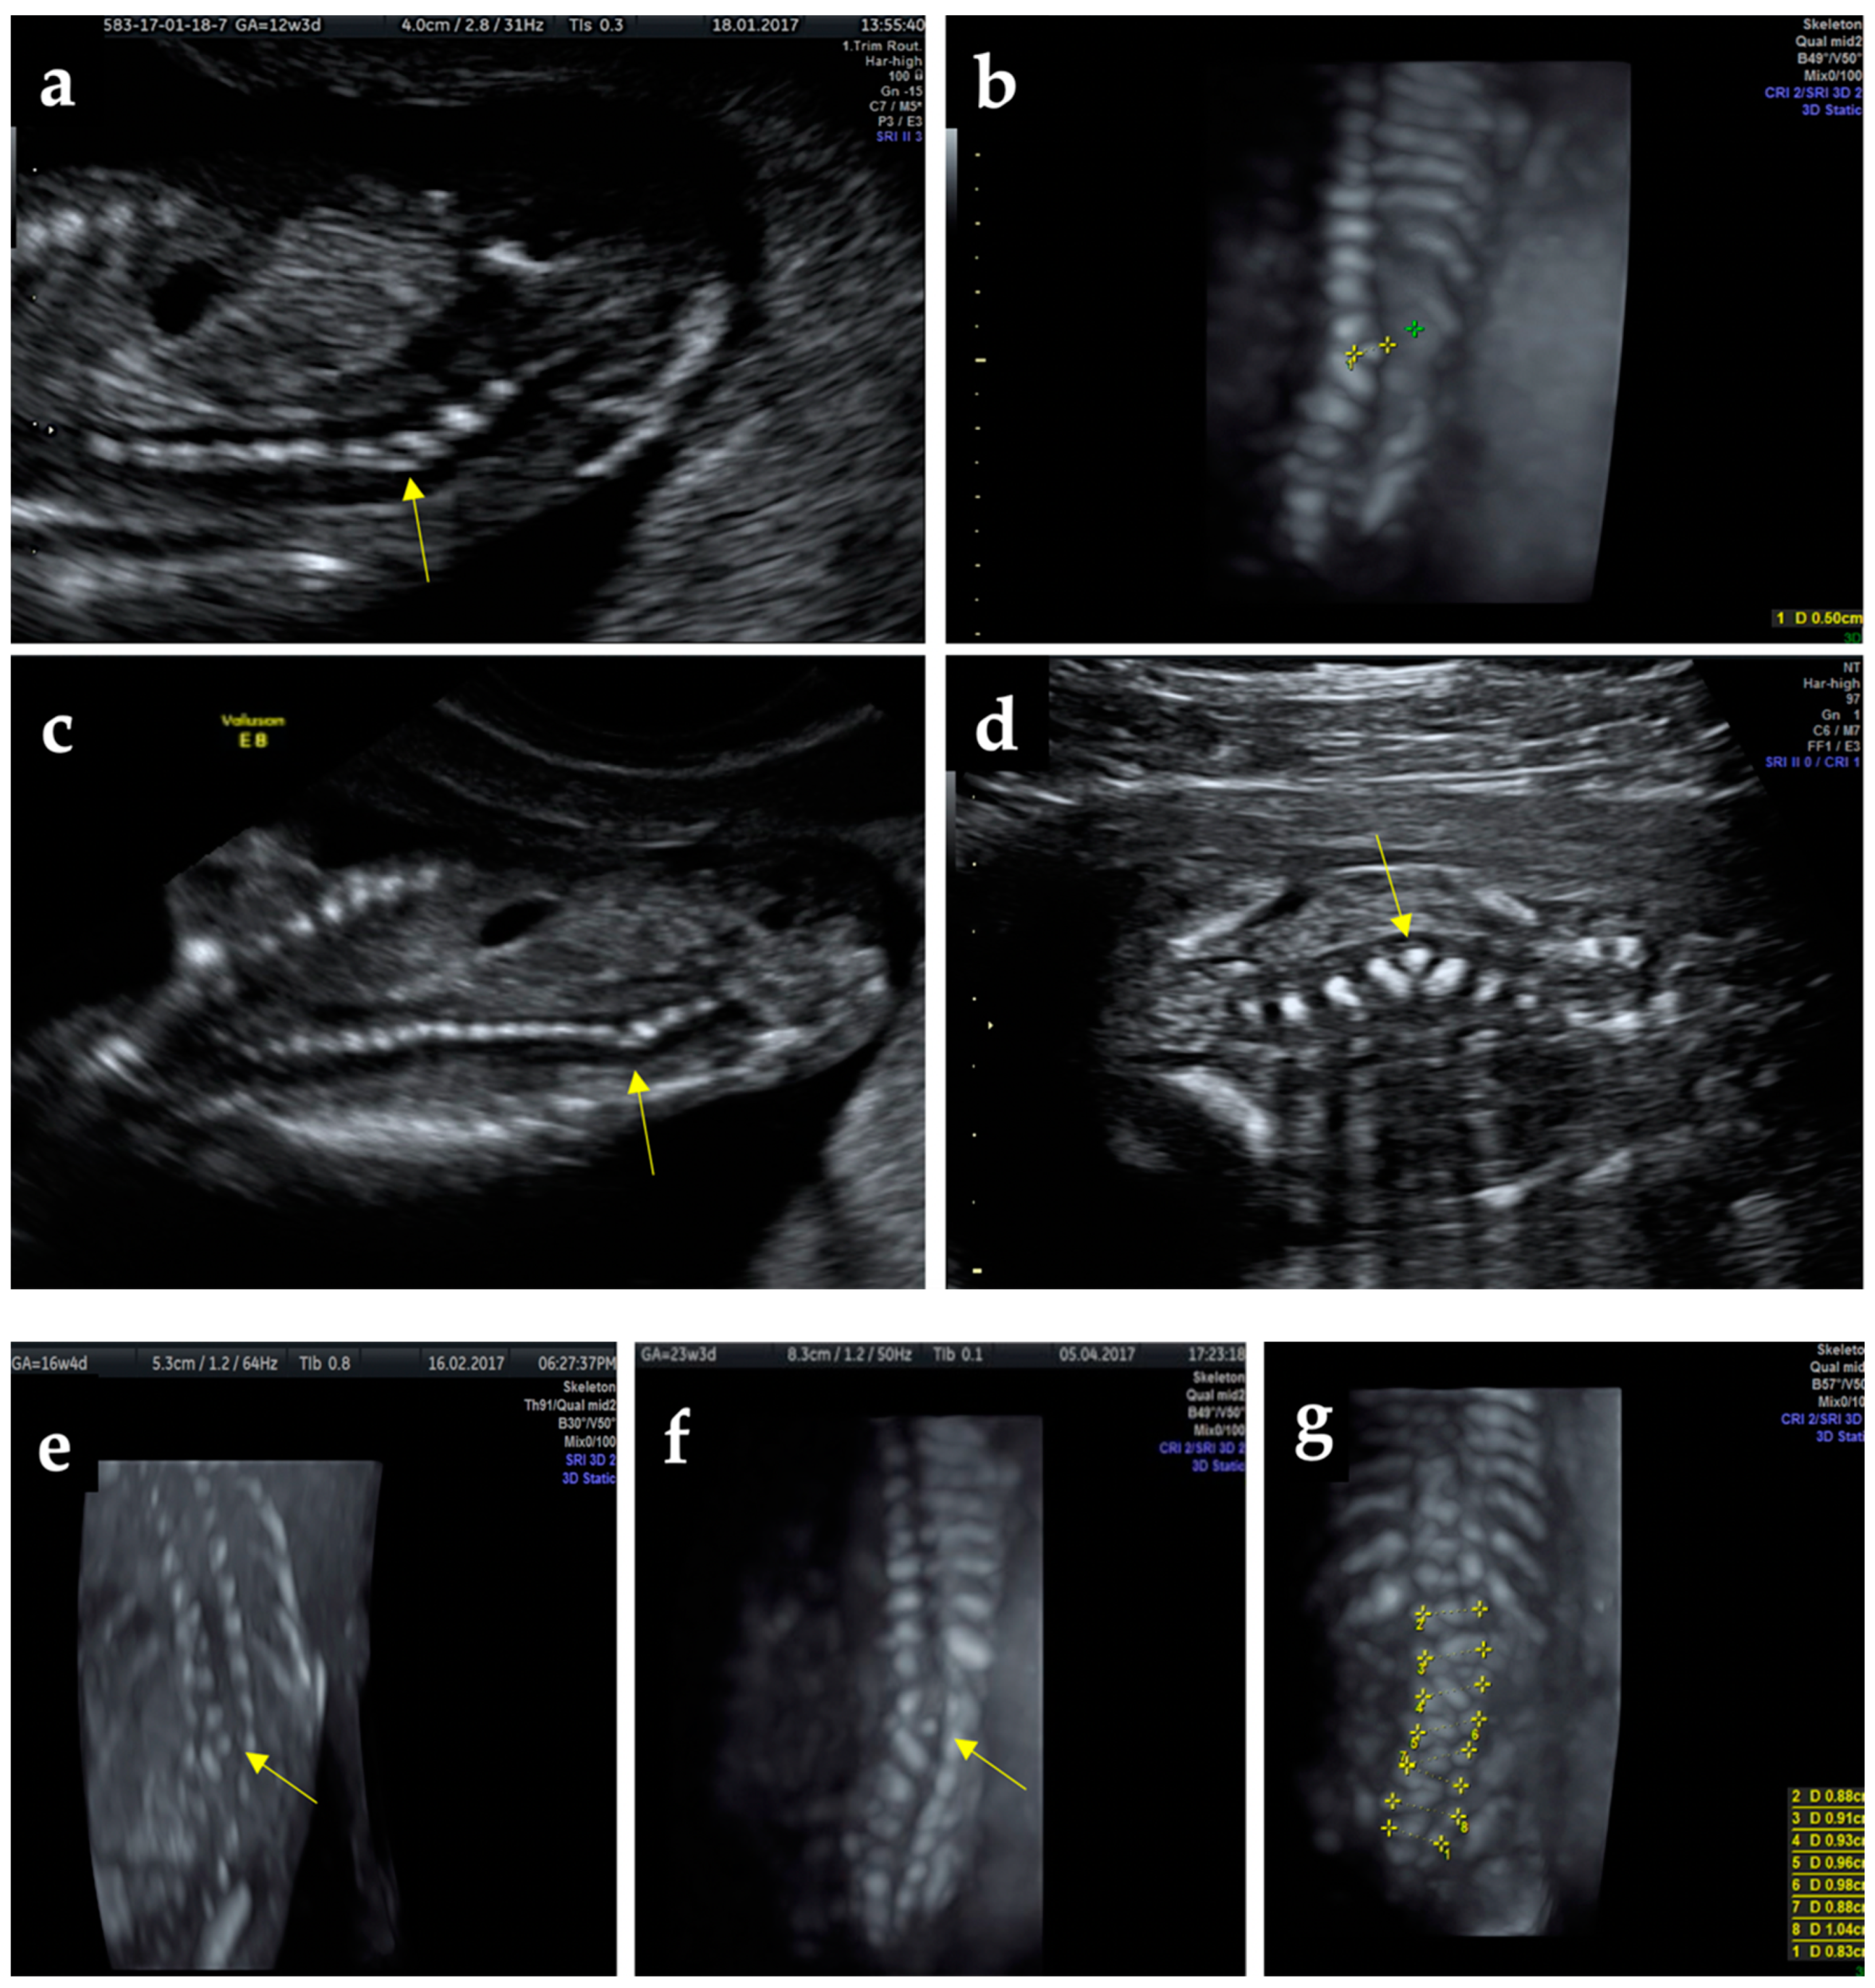

At 8 months after delivery, a routine consultation revealed the presence of an approximately 3 × 4 cm wide plaque on the right of the spine, without reflection at the skin, with mild scoliosis, suggesting the welding of the transverse process L3–L4 (Figure 2).

Figure 2.

At 8 months after delivery, a physical examination identified a mild scoliosis (red line) and rectangular zone (interrupted yellow line) in front of the transverse process L3–L4.

X-ray postnatal evaluation confirmed the early prenatal ultrasonographic diagnosis (Figure 3a). The parents refused further complementary imaging (MRI) despite the medical advice. The X-ray performed in the current year revealed in the anterior-posterior face X-ray of the thoracolumbar child’s spine, the hemivertebra, along with a mild scoliosis (Figure 3b,c).

Figure 3.

X-ray findings: (a) anteroposterior face of the child’s spine at 8 months after delivery indicating hemivertebra (yellow arrow); (b) anteroposterior X-ray face of the patient spine at 4-years-old depicting hemivertebra (yellow arrow) and scoliosis (red line), (c) lateral profile of the spine focused on the thoracolumbar section revealed the hemivertebra (yellow arrow), and curvature of the spine (red line).